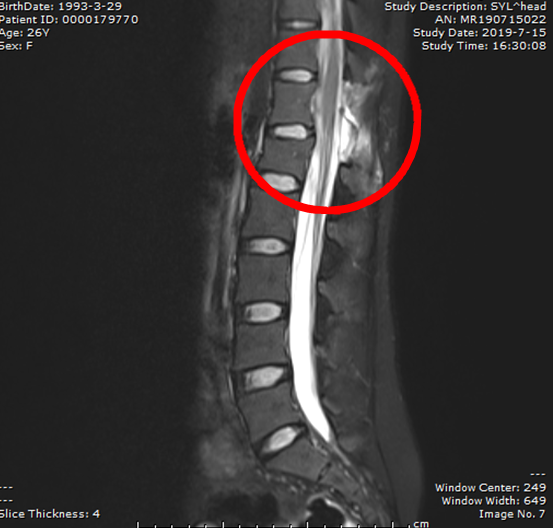

患者术后CT

由于肿瘤处于腰椎管中,位于髓外硬膜下,四处皆有神经牵连,如手术过程中稍有失误,则很可能损伤神经导致下肢瘫痪或大小便失禁,因此手术具有一定难度和风险。骨科主任张朝跃教授及张丕胜教授团队为了确保手术顺利切除肿瘤且尽可能不损伤神经,便联合神经外科专家对其会诊,并在手术过程中进行下肢及会阴部神经实时监测,术中一旦对神经有任何的牵拉、刺激或损伤,都会被准确无误的记录下来,从而让手术医师做到胸有成竹。经过了近2小时的紧张手术,骨科团队成功为患者完整切除了约7厘米*2厘米*1厘米大小的肿瘤。术后伍女士恢复良好,病检结果明确为脊膜瘤,为一种良性肿瘤。自此,伍女士及家人心上悬着的石头总算是彻底落了地。急诊电话:0736-2120120